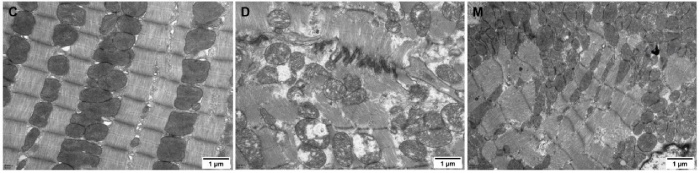

該研究利用透射電鏡測(cè)定了MOTS-c對(duì)糖尿病心肌超微結(jié)構(gòu)的影響。糖尿病引起心肌纖維排列紊亂和線粒體結(jié)構(gòu)的異常改變,包括心肌細(xì)胞排列不規(guī)則、嵴破裂、腫脹和空泡化(圖2)。MOTS-c治療糖尿病大鼠顯著降低心肌線粒體損傷,改善心肌纖維和線粒體結(jié)構(gòu)(圖2)。研究還通過測(cè)定檸檬酸合酶的活性,測(cè)定了線粒體功能。D組大鼠檸檬酸合酶的活性顯著降低,C組和M組的檸檬酸合酶的活性無統(tǒng)計(jì)學(xué)差異(圖3g)。

圖2. 各組大鼠心肌組織透射電鏡圖像